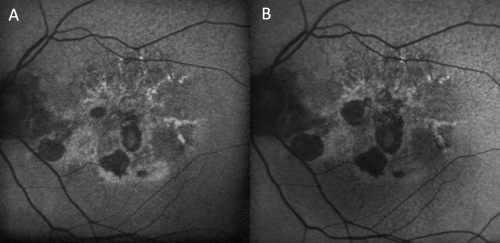

Fundus autofluorescence (FAF) is a non-invasive imaging modality that has become increasingly popular in both research and clinical settings due to its ability to map naturally and pathologically occurring fluorophores in the posterior pole. FAF was first utilized for in vivo fundus imaging in 1995 when Delori et al utilized a novel fundus spectrophotometer to characterize the intrinsic autofluorescent properties of the human retina.[1] Over time there have been many technological advancements that have allowed for the development of numerous commercially available FAF devices, with each device offering a unique set of advantages and disadvantages based on the imaging type utilized (e.g. confocal scanning laser ophthalmoscope, ultra-widefield confocal scanning laser ophthalmoscope, broad line fundus imaging, fundus camera), the excitation wavelength employed (e.g. green short-wavelength, blue short-wavelength, near-infrared) and the field of view desired.

Unlike fluorescein angiography, FAF does not require the injection of a fluorescein dye in order to image the retina, but rather utilizes the fluorescent properties of lipofuscin within the retinal pigment epithelium (RPE) to create an image. Lipofuscin, a byproduct of lysosomal breakdown of photoreceptor outer segments, is composed of numerous bisretinoids including A2E, A2PE, isoA2E, and A2-DHP-PE. When subjected to a light source, these bisretinoids absorb blue light with a peak excitation wavelength of 470nm and emit yellow-green light with a peak wavelength of 600nm, depending on the chemical makeup of the lipofuscin. A detector is then used to record the emission signals and create an image that acts as a density map of lipofuscin, with brighter areas representing regions of increased lipofuscin density. Since many retinal pathologies often lead to RPE dysfunction and an accumulation of lipofuscin, abnormal patterns of autofluorescence (AF) on FAF imaging can act as markers for retinal disease.

Abnormal Fundus Autofluorescence

Abnormal fundus autofluorescence is any pattern of AF that deviates from the classic appearance of a normal fundus as previously described.

Abnormal regions of hyper-autofluoresence (AF) are a result of increased levels of lipofuscin/compounds with similar autofluorescent spectra, or increased transmission of fluorescence. Some notable causes of hyper-AF include:

- Increased RPE lipofuscin secondary to RPE dysfunction

- Presence of subretinal autofluorescent material (eg. vitelliform lesions, blood breakdown products, certain types of drusen, subretinal fluid in central serous chorioretinopathy)

Abnormal regions of hypo-autofluorescence (AF) are a result of decreased levels of lipofuscin, decreased RPE density, or blockage of fluorescence. Some notable causes of hypo-AF include:

- Decreased RPE lipofuscin (eg RPE atrophy or RPE tears)

- Acute intraretinal or subretinal hemorrhage

- Fibrosis/scar tissue